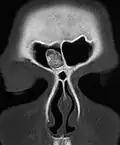

Osteoma of the frontal sinus seen on x-ray -

Osteoma of the frontal sinus on CT -